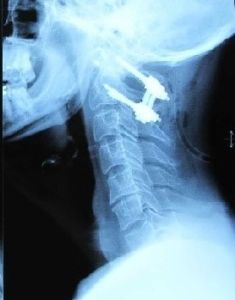

3.影像學檢查 主要依據X線平片所見,包括正位、側位及開口位,但在急診骨折情況下攝片難以獲得理想的開口位片。 CT及 MRI等亦可選用,主要用來對骨折類型、齒突先天發育狀態及脊髓受壓情況的判定。

主要依據X線平片所見,包括正位、側位及開口位,但在急診骨折情況下攝片難以獲得理想的開口位片。CT及MRI等亦可選用,主要用來對骨折類型、齒突先天發育狀態及脊髓受壓情況的判定。疾病治療

2.固定方式 對輕度移位、復位後對位穩定或無移位的齒突骨折者可採用顱骨牽引的方式,待局部纖維癒合後(4~6周),再以頭-頸-胸石膏固定6~8周。對移位明顯、復位後仍不穩定及陳舊性者,多需採用開放復位及內固定術。除傳統的後路融合術外,當前多主張自頸前路暴露頸1~2椎節,行齒突骨折復位加螺釘1~2枚內固定術(圖2),或行雙側寰樞椎間關節植骨融合術(圖3),但齒突螺釘內固定時,由於齒突較細小,如操作不當,或是術後遇有頭頂部外傷或平地跌倒等,易引起齒突粉碎性骨折或螺釘斷裂,以致導致手術失敗,應注意避免。